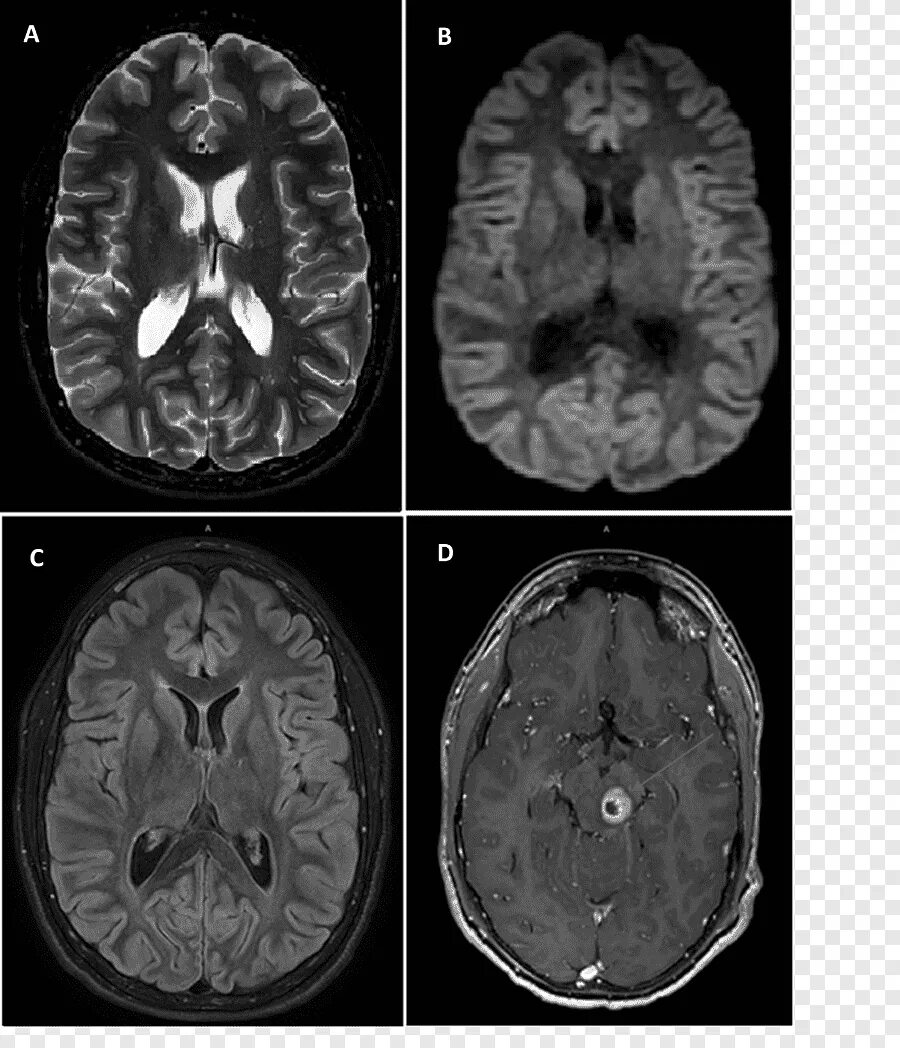

Мрт диффузия всего тела